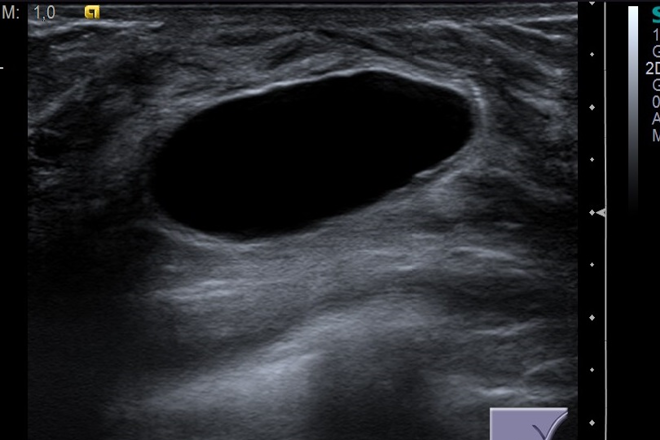

La aspiración con aguja fina de las lesiones intramamarias es la primera maniobra diagnóstica. Los estudios de imagen mamaria, especialmente la mastografía, son fundamentales. Aunque se prefiere el ultrasonido por su capacidad para diferenciar entre masas sólidas y quísticas, la mastografía sigue siendo el estudio de elección en muchos casos. En cuanto al tratamiento, una vez realizado el diagnóstico de cáncer, la estadificación es indispensable, y la resonancia magnética resulta segura durante el embarazo para una correcta evaluación.